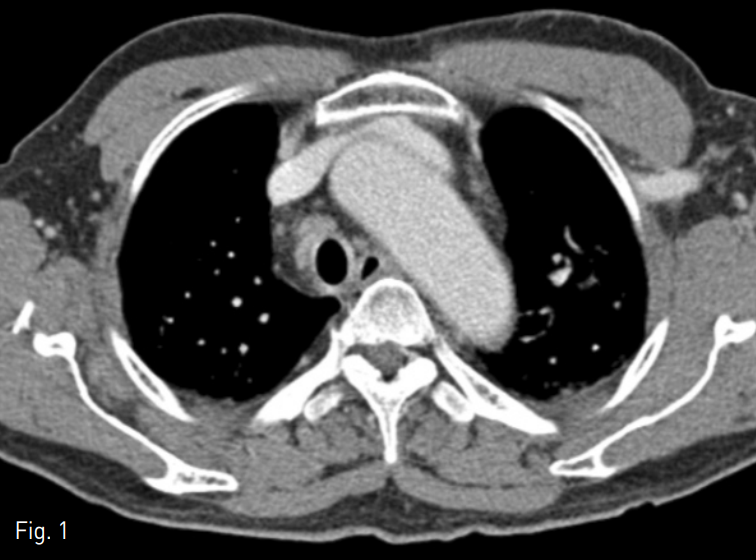

이후 Amplatz gooseneck snare (ev3, Minneapolis, USA)를 이용하여 스텐트의 중간부위를 포획하였으나 스텐트의 말단부가 sheath를 통과하기에는 충분하게 접히지 않음 (Fig. 4). 이에 또 다른 Goose neck snare를 이용하여 스텐트의 말단부를 포획하였고 스텐트를 femoral sheath 내부로 끄집어내어 몸 밖으로 성공적으로 제거 할 수 있었음 (Fig. 5).

Fig. 4

The stent was captured with a nitinol loop.